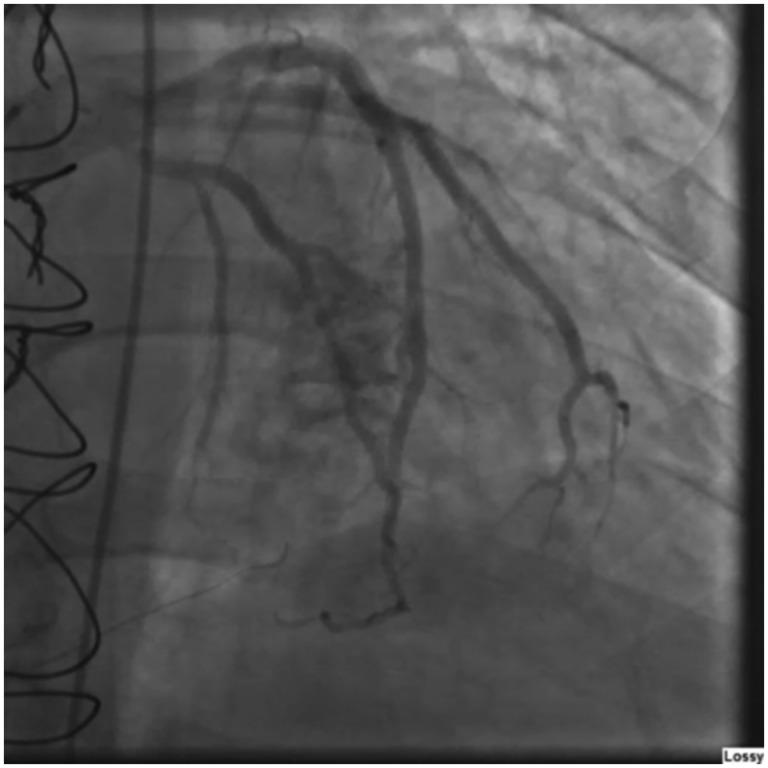

A coronary cameral fistula treated with coil embolization.

A 56-year-old man who had twice previously undergone orthotopic heart transplantation was admitted with dyspnea and heart failure symptoms. A biopsy excluded rejection. Left heart catheterization revealed a coronary cameral fistula. After the patient was given mild diuretics, his condition improved. No significant fistula flow was detected, and he was discharged. Several months later, the patient was readmitted with worsening chest pain and dyspnea. Left ventricular end-diastolic pressure and flow through the fistula were increased. To correct the coronary cameral fistula, we performed a coil embolization without complications. Several months later at follow-up, the patient's symptoms had resolved, and his left ventricular end-diastolic pressure had normalized. We conclude that coronary fistulas may be caused by trauma to the heart during the de-airing process, which may be prevented in the future with the development of safer and more effective de-airing techniques.